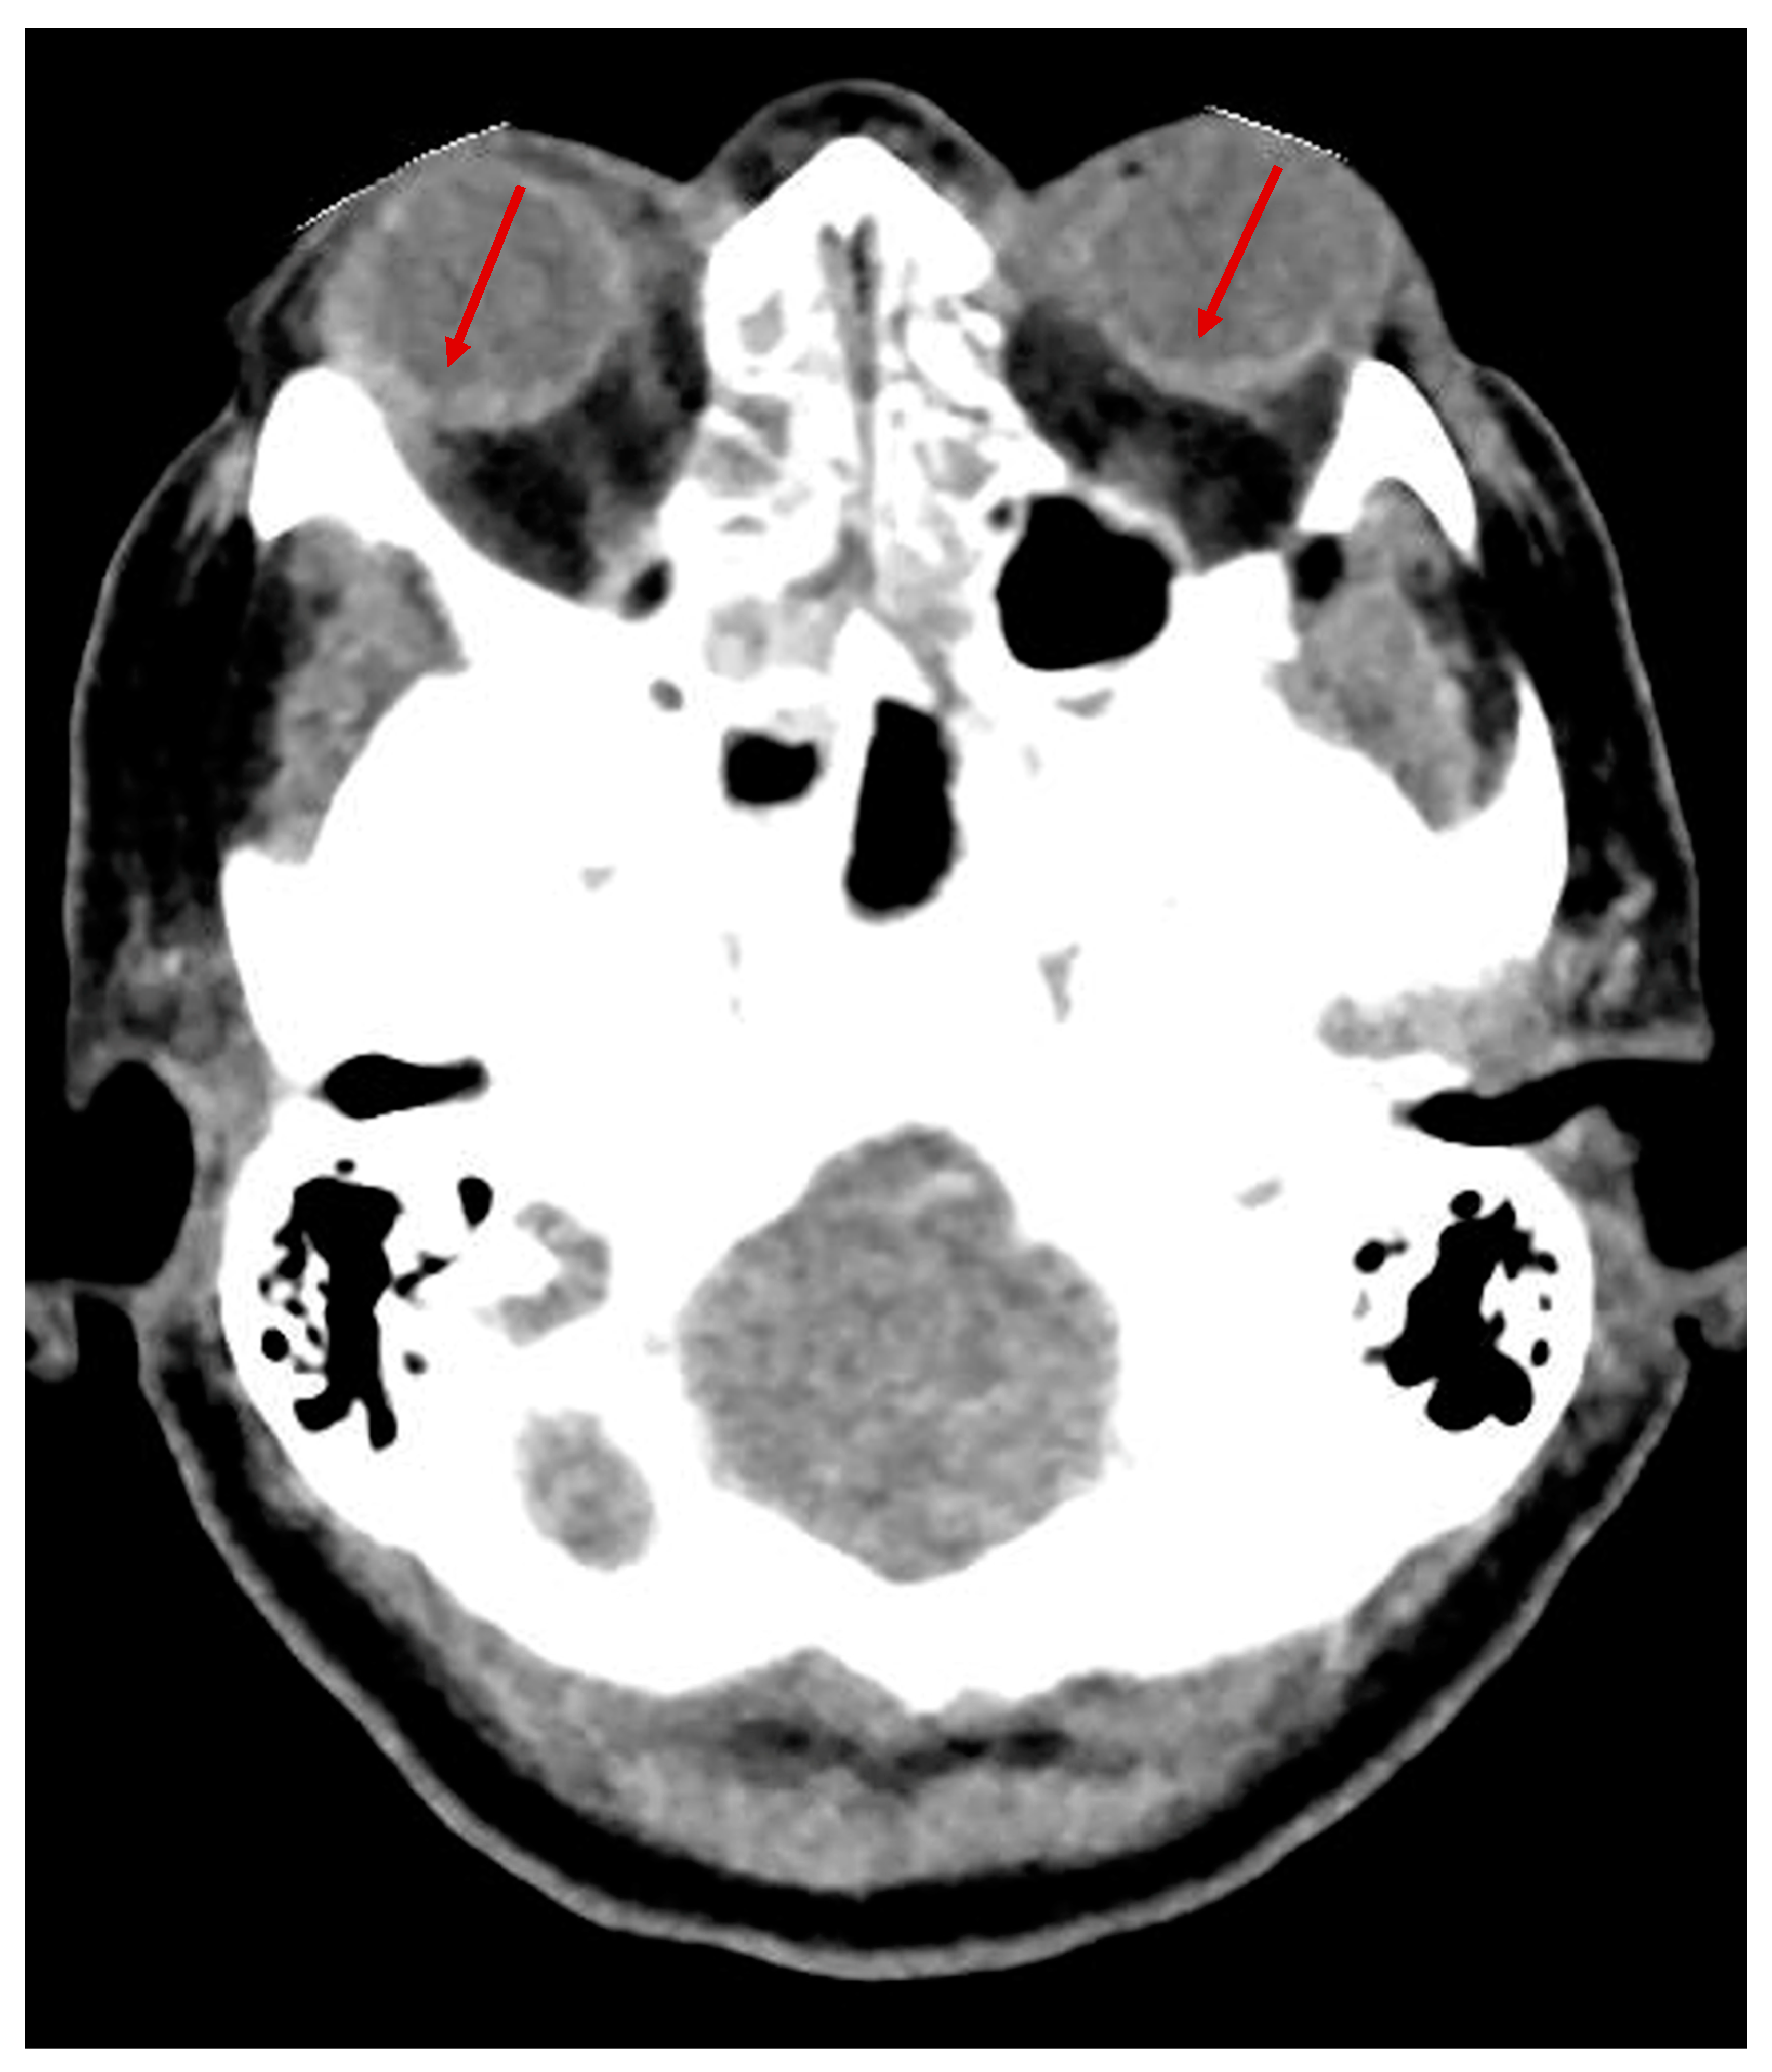

After several weeks, the patient complained of visual deficit. A fundoscopic examination at the bedside performed 44 days post-extubation revealed an extensive vitreous hemorrhage in both eyes. The posterior pole could not be visualized. The visual status could not be determined due to the patient’s poor cooperation. A vitrectomy was performed on the left eye. Postoperatively, the patient was able to visually track a light source, but her poor cognitive status prevented a more precise evaluation of visual function. The bilateral TS was not initially detected upon the first examination of the cerebral CT scan performed 20 days after admission (Figure 1), but was retrospectively confirmed after reviewing the CT images with a senior neuroradiologist. The patient slowly progressed and was discharged to a neurological rehabilitation center after 39 days of hospital stay in the ANR unit.

Figure 1. No-contrast brain CT scan of patient 1 showing bilateral Terson’s syndrome (arrows); diagnosis was retrospectively confirmed by a senior neuroradiologist.